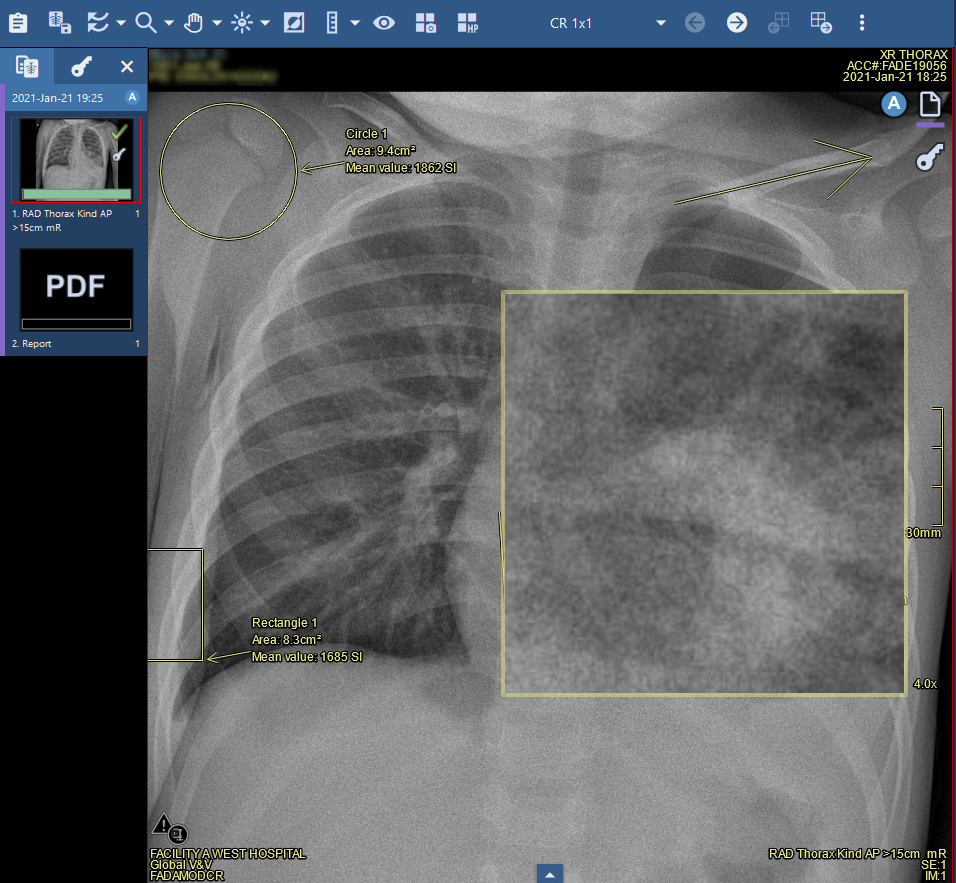

Figure: Use the zoom lens tool to magnify areas of interest

The zoom lens tool creates a magnification overlay focusing on your mouse location.